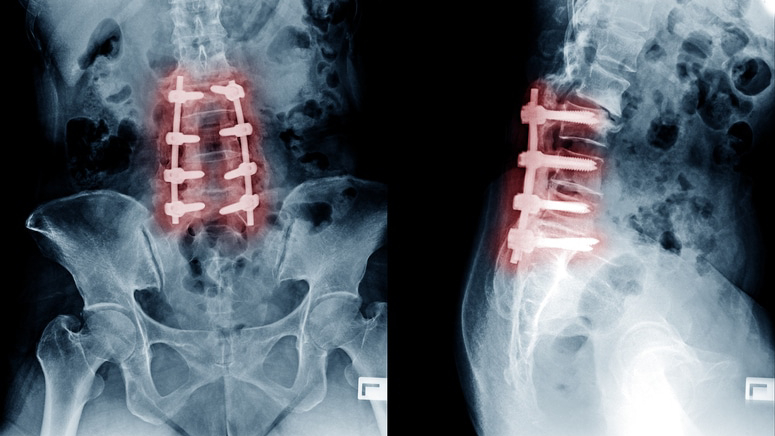

دمج الفقرات القطنية واستبدال الديسك بالتداخل المحدود عبر الثقوب (TLIF) هو